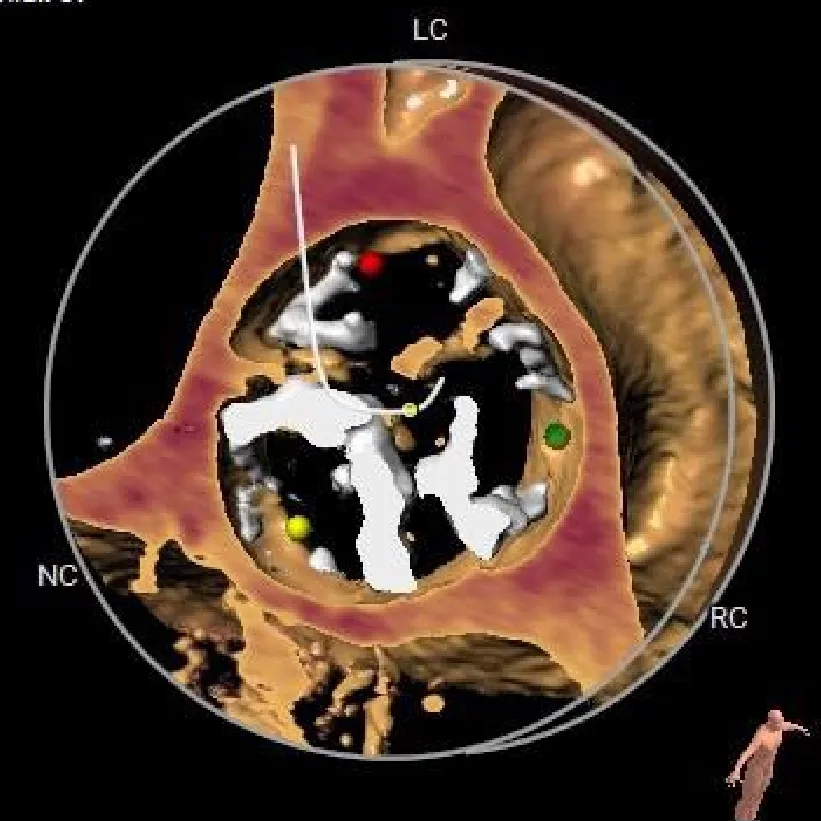

VR图

钙化积分

601mm3

SOV:

28*27.8*26.8mm

STJ:

26.4mm